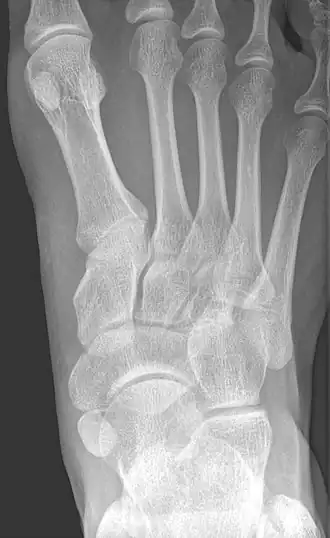

Type 2 -

Cornuate navicular bone -